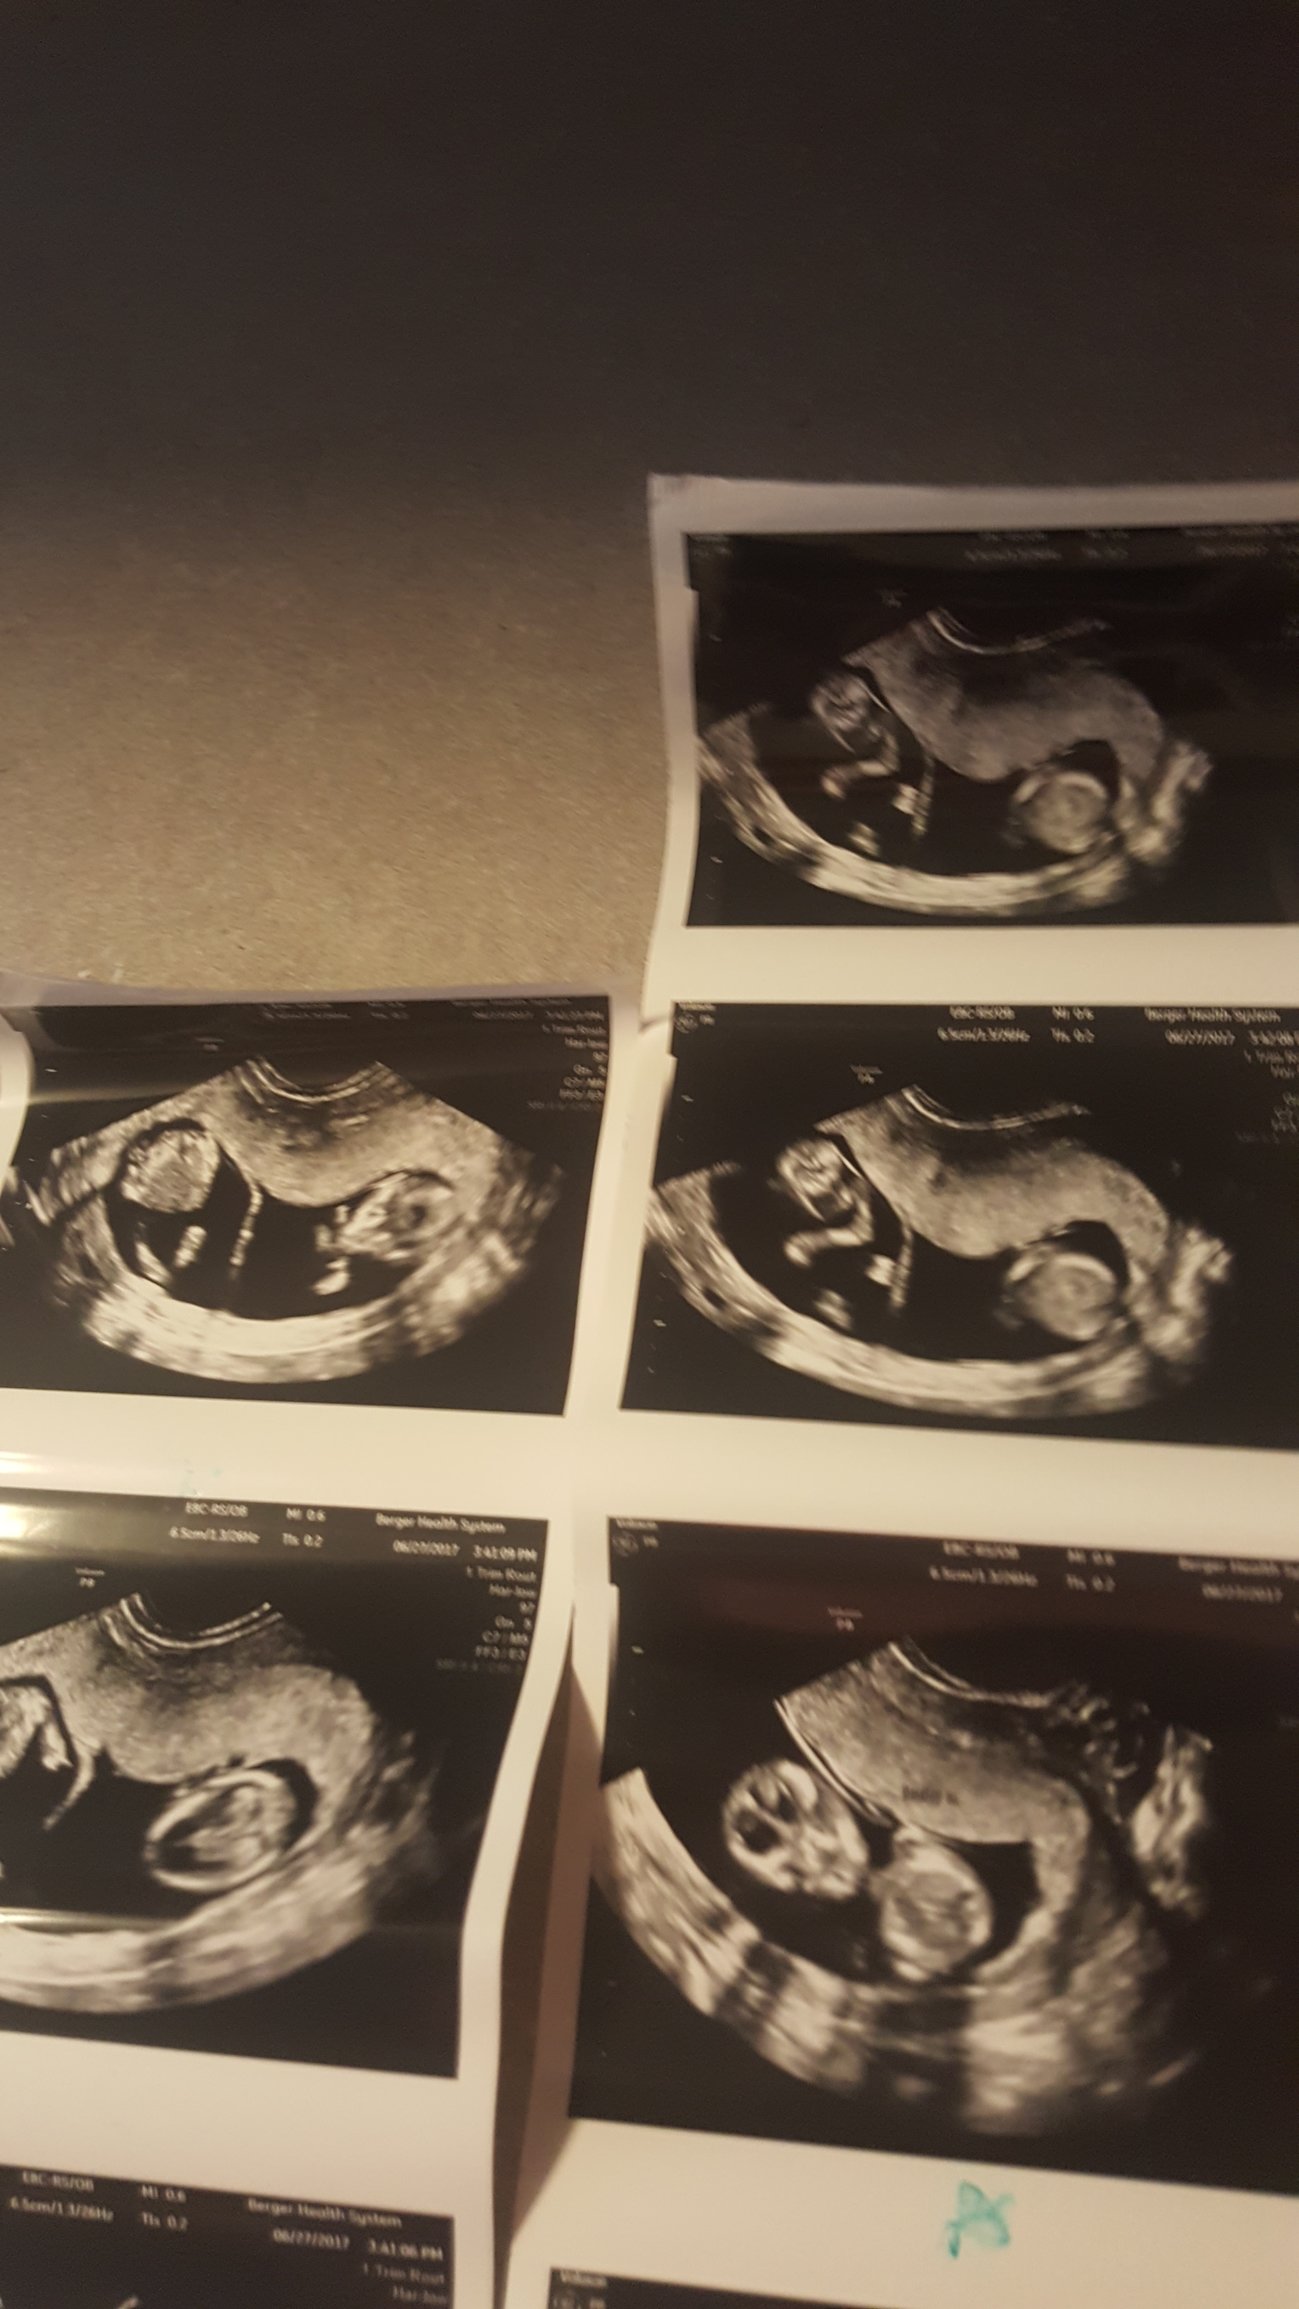

Had my first appointment yesterday 6/22 and instead of measuring my suspected 7w6d we are at 12w3d! The picture isn't the greatest since the baby was moving around like CRAZY but we are thrilled!

Went in for our first (8 week) appointment to find out SURPRISE; we are actually 12 weeks pregnant.

New due date of January 5th.